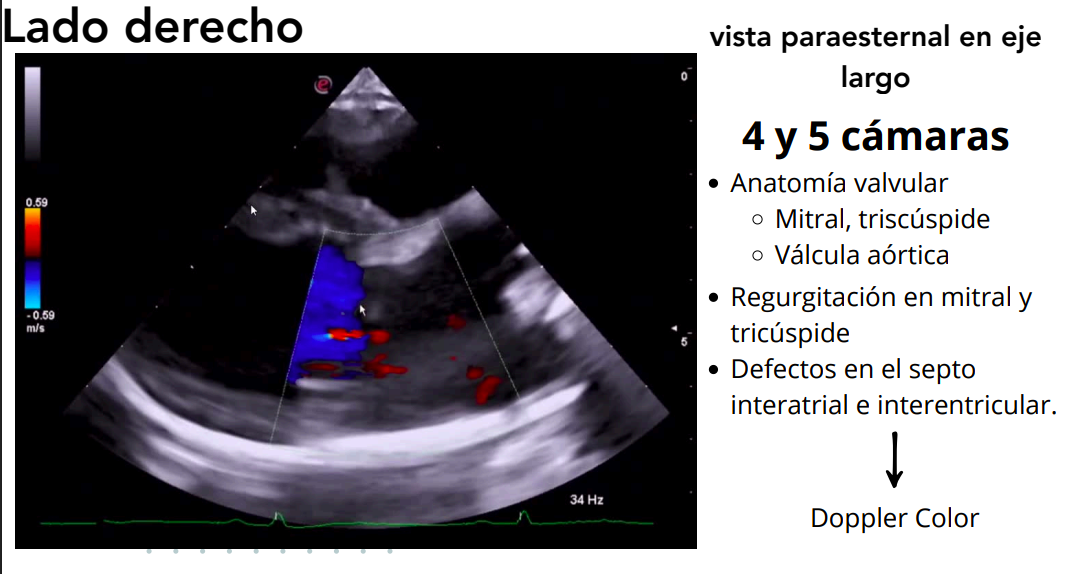

Vista paraesternal en eje largo

- 4 cámaras y 5 cámaras (incluye tracto de salida del VI).

- Evaluación de:

- Válvulas mitral, tricúspide y aórtica.

- Regurgitaciones valvulares.

- Defectos en septos interatrial e interventricular.

Doppler color: muestra regurgitaciones.